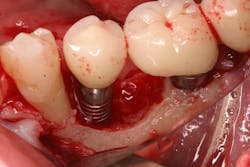

Once again, the literature is replete with case reports and case series describing soft- and hard-tissue loss due to excess dental cement left at the time of implant crown insertion.8 In one study, 90% of the implant crowns inserted with cement exhibiting inflammation and bleeding upon probing were due to cement in the peri-implant sulcus.9 Cement acts as a nidus for bacteria and induces a rapid hard-tissue loss around the dental implant fixture (figures 2 and 3).